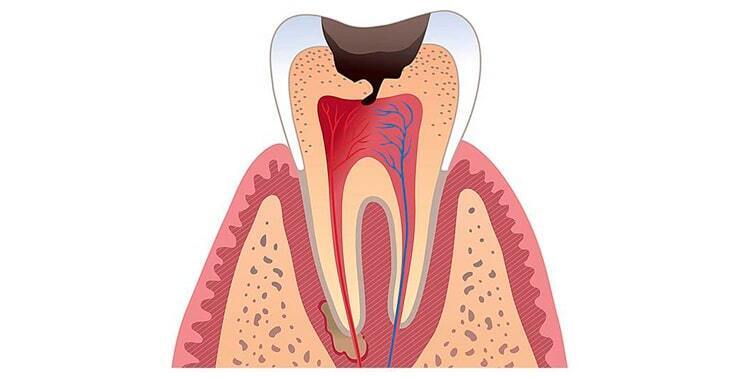

Кариес зубов – заболевание, возникающее вследствие воспаления, вызванного попаданием в полость рта болезнетворных микроорганизмов.

Корневое каналовое лечение. Если кариес или травма повредила зубной канал.